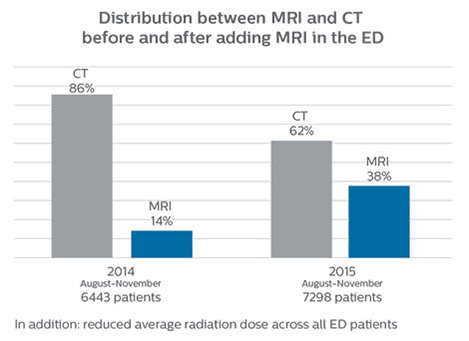

Since 2012, St. Joseph’s Hospital and Medical Center in Phoenix, Arizona, USA, has had an ED dedicated to neurological patients. In 2015, John Karis, MD, of the Barrow Neurological Institute at St Joseph’s spearheaded a project to place an MRI system in the Neuro ED. He stressed the added prognostic value of having an emergency MRI, and the importance of reducing radiation doses, particularly in patients for whom a CT scan was not the optimal test.

efficient as CT for referring physicians, then physicians would probably prefer MRI over CT in part of the cases. Reducing the number of CT scans for patients less than 40 years of age without significant acute findings, such as acute stroke, was also a main reason for introducing MRI into the ED. “MRI is a better test for identifying soft tissue abnormalities in the brain. What really influenced the decision on the administrative side, was the total radiation dose received by ED patients, and how this could be reduced by introducing MRI in the ED”.

Since 2012, St. Joseph’s Hospital and Medical Center in Phoenix, Arizona, USA, has had an ED dedicated to neurological patients. In 2015, John Karis, MD, of the Barrow Neurological Institute at St Joseph’s spearheaded a project to place an MRI system in the Neuro ED. He stressed the added prognostic value of having an emergency MRI, and the importance of reducing radiation doses, particularly in patients for whom a CT scan was not the optimal test.

Changing established behaviors

The transition away from a predominantly CT-based ED began by educating physicians about the advantages of MRI in the emergency setting, when to use MRI, and the importance of targeted exams instead of broader, non-targeted exams. Some resistance to the change was anticipated, as it was disrupting established routines, so a reasonable amount of time was planned for educating referrers, neuroradiologists and neurosurgeons, as well as residents and fellows. However, less time than anticipated was needed: all involved were already familiar with MRI and, more importantly, they were easily persuaded on learning about the 10-minute exam duration with MRI.

Future plans: expansion to stroke and TIA patients

At St. Joseph’s Hospital and Medical Center, the dedicated MRI system in the ED has been shown to efficiently provide high quality MR images that assist physicians in making informed decisions on patient diagnoses and take a more definitive decision on follow-up. The decision to have a dedicated ED MRI has resulted in rapid patient turnaround, efficient patient management, and substantial reductions in radiation dose.

For Dr. Karis, the next goals for the neuro ED include converting the exams for acute stroke and TIA patients from CT to MRI, offering an alternative management option for these patients. Also, collaboration between other departments is currently underway, encouraging the performance of targeted exams with the ED MRI. These improvements in workflow and faster turnaround times may result in further reductions in scanning time.